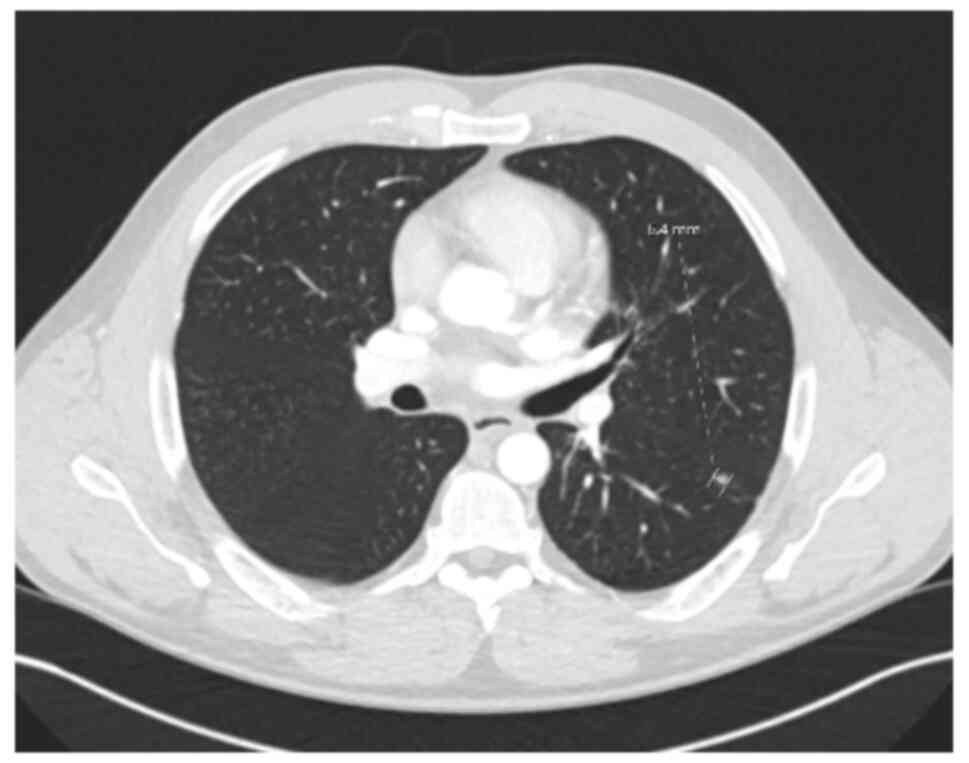

The patient remained in a good condition clinically, although mild biochemical evidence of recurrent PSC was noted. In June, 2022, a solitary left lower lobe lung nodule was detected on surveillance imaging (Fig. 7). Wedge resection confirmed a 5-mm metastatic lesion from the original hCCA (pTisN0R0). The patient was commenced on capecitabine in November, 2022, typically administered at a dose of 1,250 mg/m2 twice daily on days 1-14 of a 21-day cycle. He completed seven cycles by April, 2023 with no observed toxicities.

Axial contrast-enhanced computed

tomography scan demonstrating a solitary pulmonary nodule in the

left lower lobe, identified on routine surveillance in June,

2022.

Figure 7

Axial contrast-enhanced computed tomography scan demonstrating a solitary pulmonary nodule in the left lower lobe, identified on routine surveillance in June, 2022.